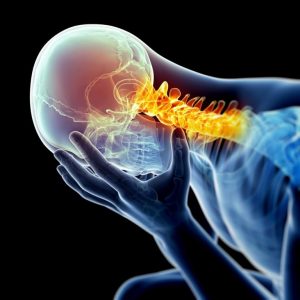

Top 10 Most Common Injuries Seen by Sports Chiropractors

Even the most seasoned athletes are not immune to pain and injuries from time to time. This is particularly the case for those who are